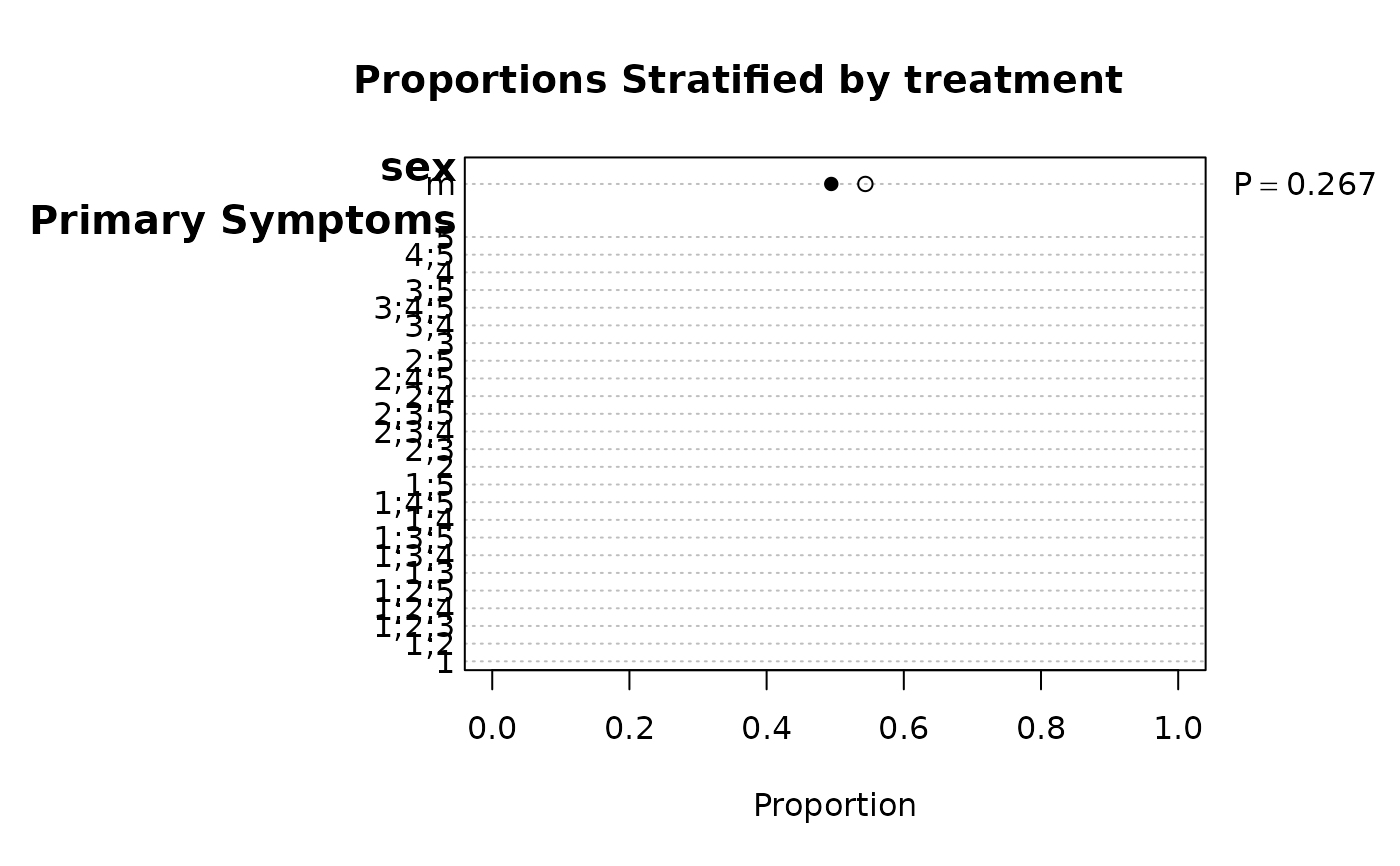

f <- summaryM(age + sex + sbp + Symptoms ~ treatment, test=TRUE)

#> |sex : m |500| 0.49 (129) | 0.54 (130) |Chi-square=1.23 d.f.=1 P=0.267|

plot(f, conType='dot', prtest='P')

plot(f, conType='dot', prtest='P')